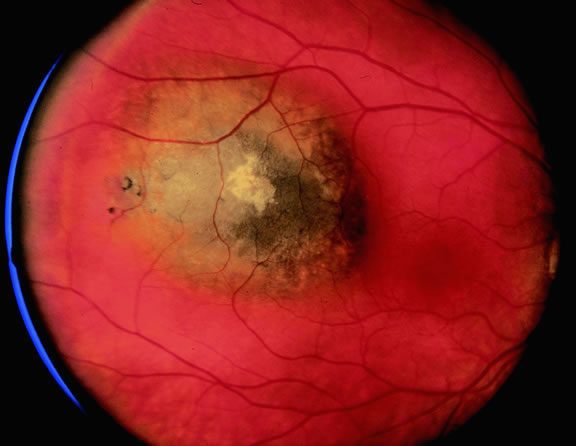

Ophthalmoscopic examination of a choroidal melanoma typically reveals a sessile or dome-shaped pigmented mass located deep to the retina (Figs. 16, 17, and 18). There often is an associated secondary nonrhegmatogenous serous detachment of the retina. Orange pigment may be located on the surface of smaller lesions.80,81 Tumors vary in pigment content and may be heavily pigmented or totally amelanotic. The differentiation of a totally amelanotic melanoma from uveal metastasis, hemangioma, lymphoma, or osteoma may be difficult. Compared with metastasis, melanoma usually is more highly elevated and drusen and RPE proliferation more evident on its surface. Ophthalmoscopy also typically shows well-defined vessels within melanoma.48 Ancillary studies such as fluorescein angiography and ultrasonography may be necessary to make the diagnosis.

Fig. 17. Pigmented choroidal melanoma. Elevated tumor has broken through Bruch's membrane.

Many choroidal melanomas have a characteristic mushroom or collar button configuration that results when the tumor breaks through Bruch's membrane (Figs. 19, 20, 21, and 22). In such cases there is often secondary choroidal, subretinal, or vitreous hemorrhage. Dilated, intrinsic vessels often are evident in the mushrooming dome of nonpigmented melanomas. The vessels are obscured in more pigmented tumors.48

Fig. 19. Fundus photo of mushroom-shaped choroidal melanoma with nonpigmented dome. Configuration indicates that tumor has ruptured through Bruch's membrane.